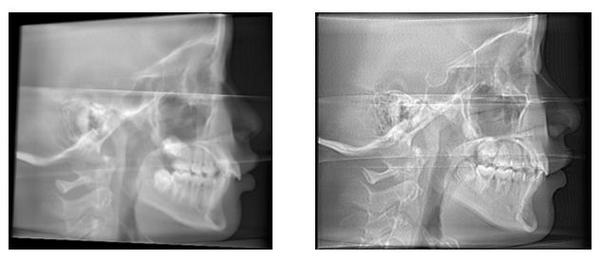

初步检查:

- 在显示器上观察影像(数字设备)或胶片(传统设备)。

- 检查关键点:

- 鼻根点(N)、蝶鞍点(S)、耳点(Po)、眶点(Or)是否清晰可见?

- 眶点(Or)和耳点(Po)是否在同一水平线上?(这是判断FH平面是否水平的关键)

- 头颅左右两侧是否对称?下颌骨升支、髁突、颧弓等结构是否双侧对称显示?

- 有无因移动导致的模糊?

- 曝光参数是否合适(密度、对比度)?

- 如有问题,必须重拍! 不准确的影像会导致错误的诊断和治疗计划。